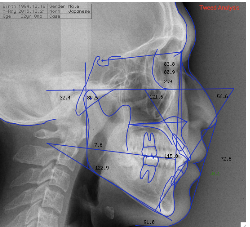

あなたの現在の横顔に、レントゲンによる骨格と歯のデータを重ね合わせ、矯正治療後のシミュレーションを初診でご覧頂くことが出来ます。矯正治療を始める前に、コンピューターとデジタルデータを使用して、あなたの治療後を予測できるシステムです。

横顔のレントゲン及び実際の横顔のデジタル画像のコンピューターへの入力の後、あなたの骨格、歯の状態に合わせて、治療を受けた場合の横顔の変化のシュミレーションを行います。